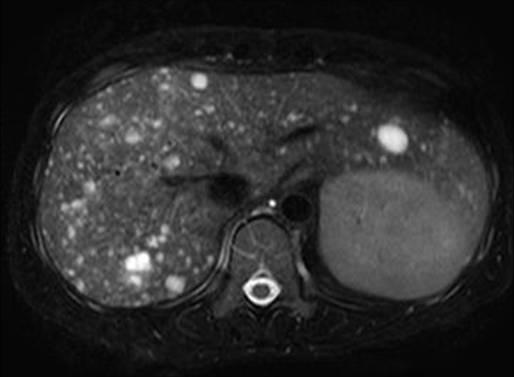

Hamartoma đường mật

» Thông tin: Nam giới – 34 tuổi.

» Lâm sàng: Kiểm tra sức khỏe.